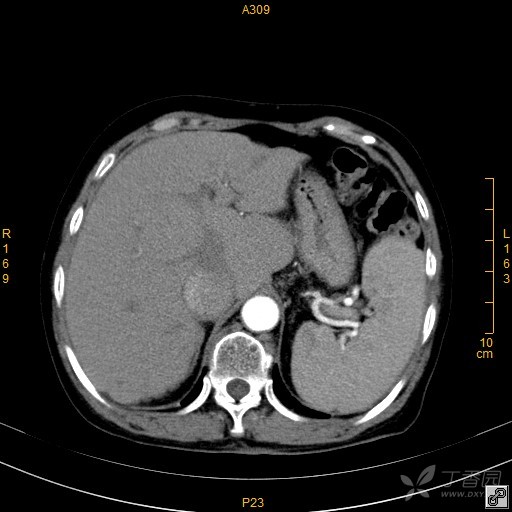

大家讨论下下腔静脉到底是怎么了,增强好奇怪. [病例帖]

肝左 叶 胃 肝右 叶 脾 下腔 静脉 脊髓 腹主 动脉

影像学上腹部ctppt 门静 脉 胃 腹主 动脉 肝右 叶 脾 膈脚 下腔 静脉